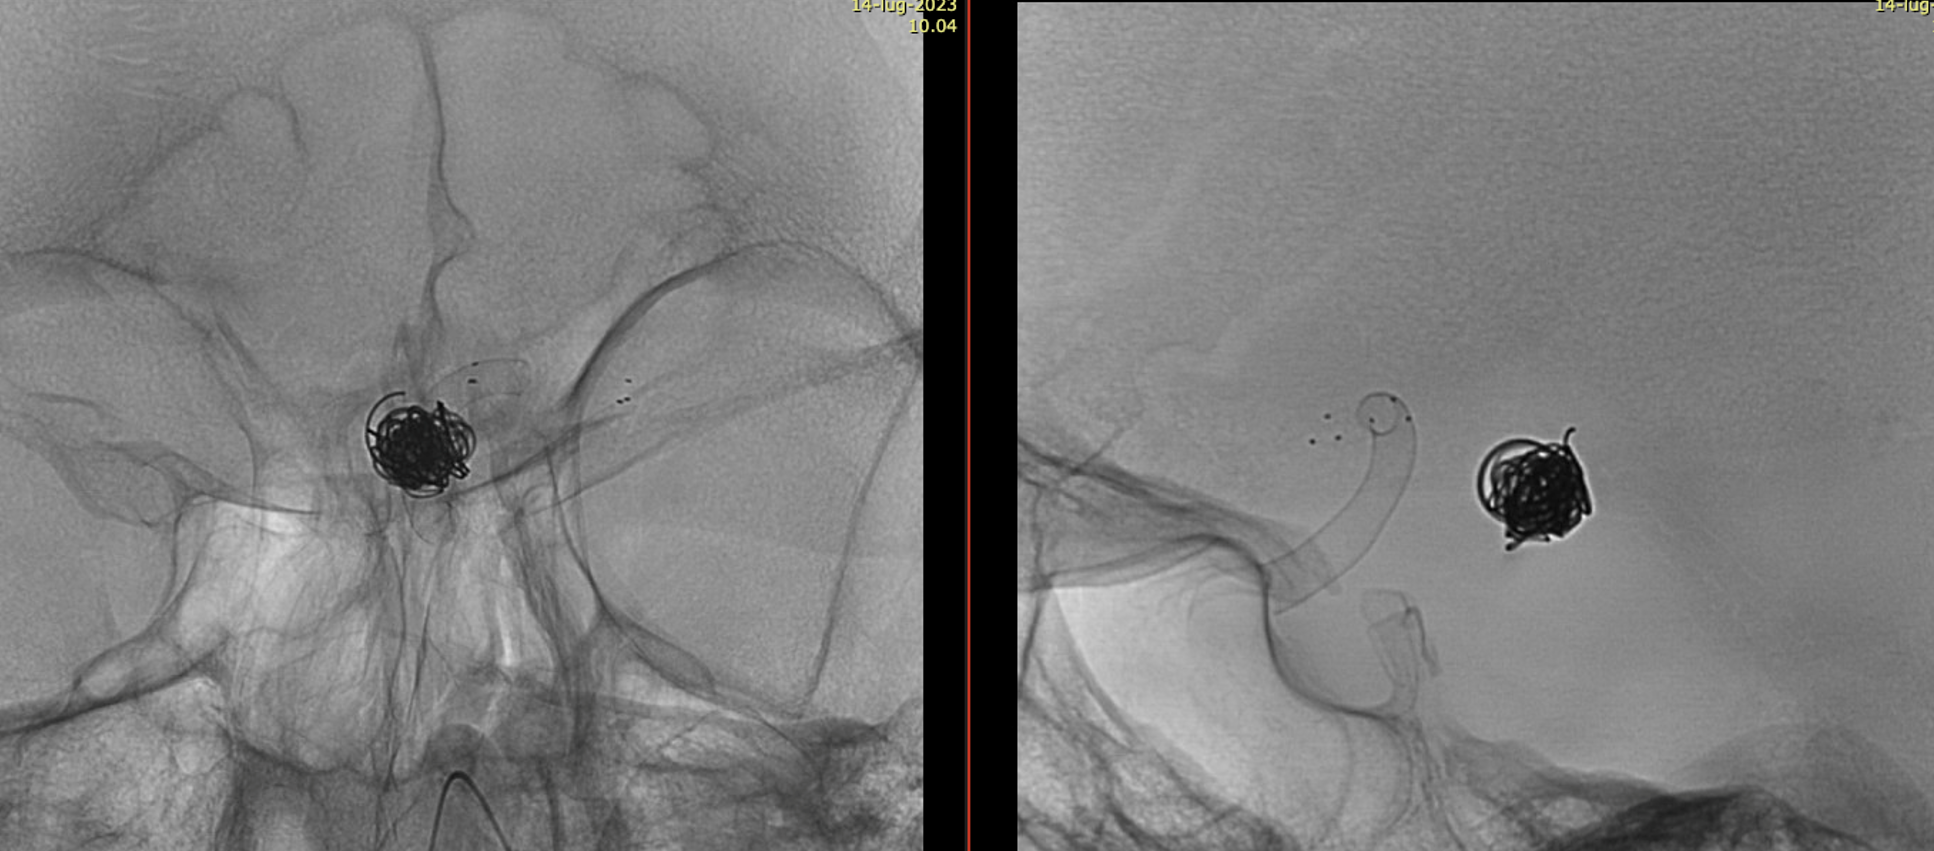

Important Case of Aggressive Anterior Choroidal Aneurysm

This is a specific subtype of ever-growing choroidal aneurysm that is extremely difficult to solve without complete occlusion of the aneurysm and the choroidal artery. Fortunately, perhaps because of the unique aneurysm biology, choroidal occlusion tends to be mildly or not at all symptomatic.

A young man with an unruptured but symptomatic dissecting aneurysm at the origin of the Anterior Choroidal artery. Treated in acute phase with coils; in the meantime the aneurysm has grown.

A Silk Vista was implanted a couple of weeks after coiling

Immediately after the release of the SV, we saw a minimum movement of the distal end to fishmouthing

A Credo stent was used to keep the SV apposed to the vessel wall

One month later the aneurysm was still growing — as they frequently do.

A Bentley Coronary Stent 3 x 8 mm was implanted, progressively inflated (even with a 3.5 PTA balloon) until no more contrast entered the aneurysm. The USA version of Bentley is the Papyrus — Bentley is better.

Noncontrast / dry Vaso-CT, 22 cm FOV 20 seconds acquisition, followed by a secondary reconstruction with 50% FOV and 5123 resolution; Thick MIP.

We can clearly see the three stents. The Credo seems too rigid and probably is not fully open in the curve. The Bentley (arrows) is a little bit overinflated (consider that at this level the coils reduce the image quality). SV is open with some irregularity.

This is the problem with using laser-cut stents for fishmouthing. Alternative is a relatively low coverage braided stent like Evo or LVIS Jr.